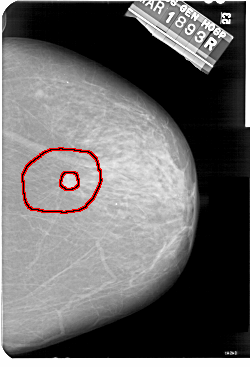

FILE: A_1573_1.RIGHT_MLO.OVERLAY

TOTAL_ABNORMALITIES 1

ABNORMALITY 1

LESION_TYPE MASS SHAPE IRREGULAR MARGINS SPICULATED

ASSESSMENT 5

SUBTLETY 3

PATHOLOGY MALIGNANT

TOTAL_OUTLINES 2

BOUNDARY

CORE